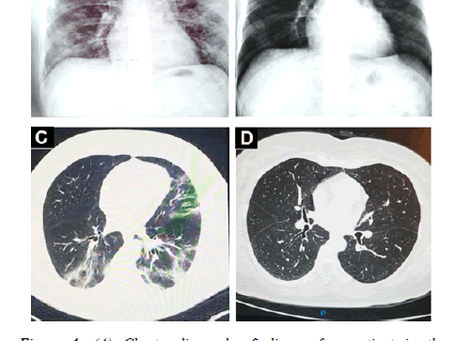

Itraconazole for COVID-19: preclinical studies and a proof-of-concept randomized clinical trial

Abstract Background The antifungal drug itraconazole exerts in vitro activity against SARS-CoV-2 in Vero and human Caco-2 cells....